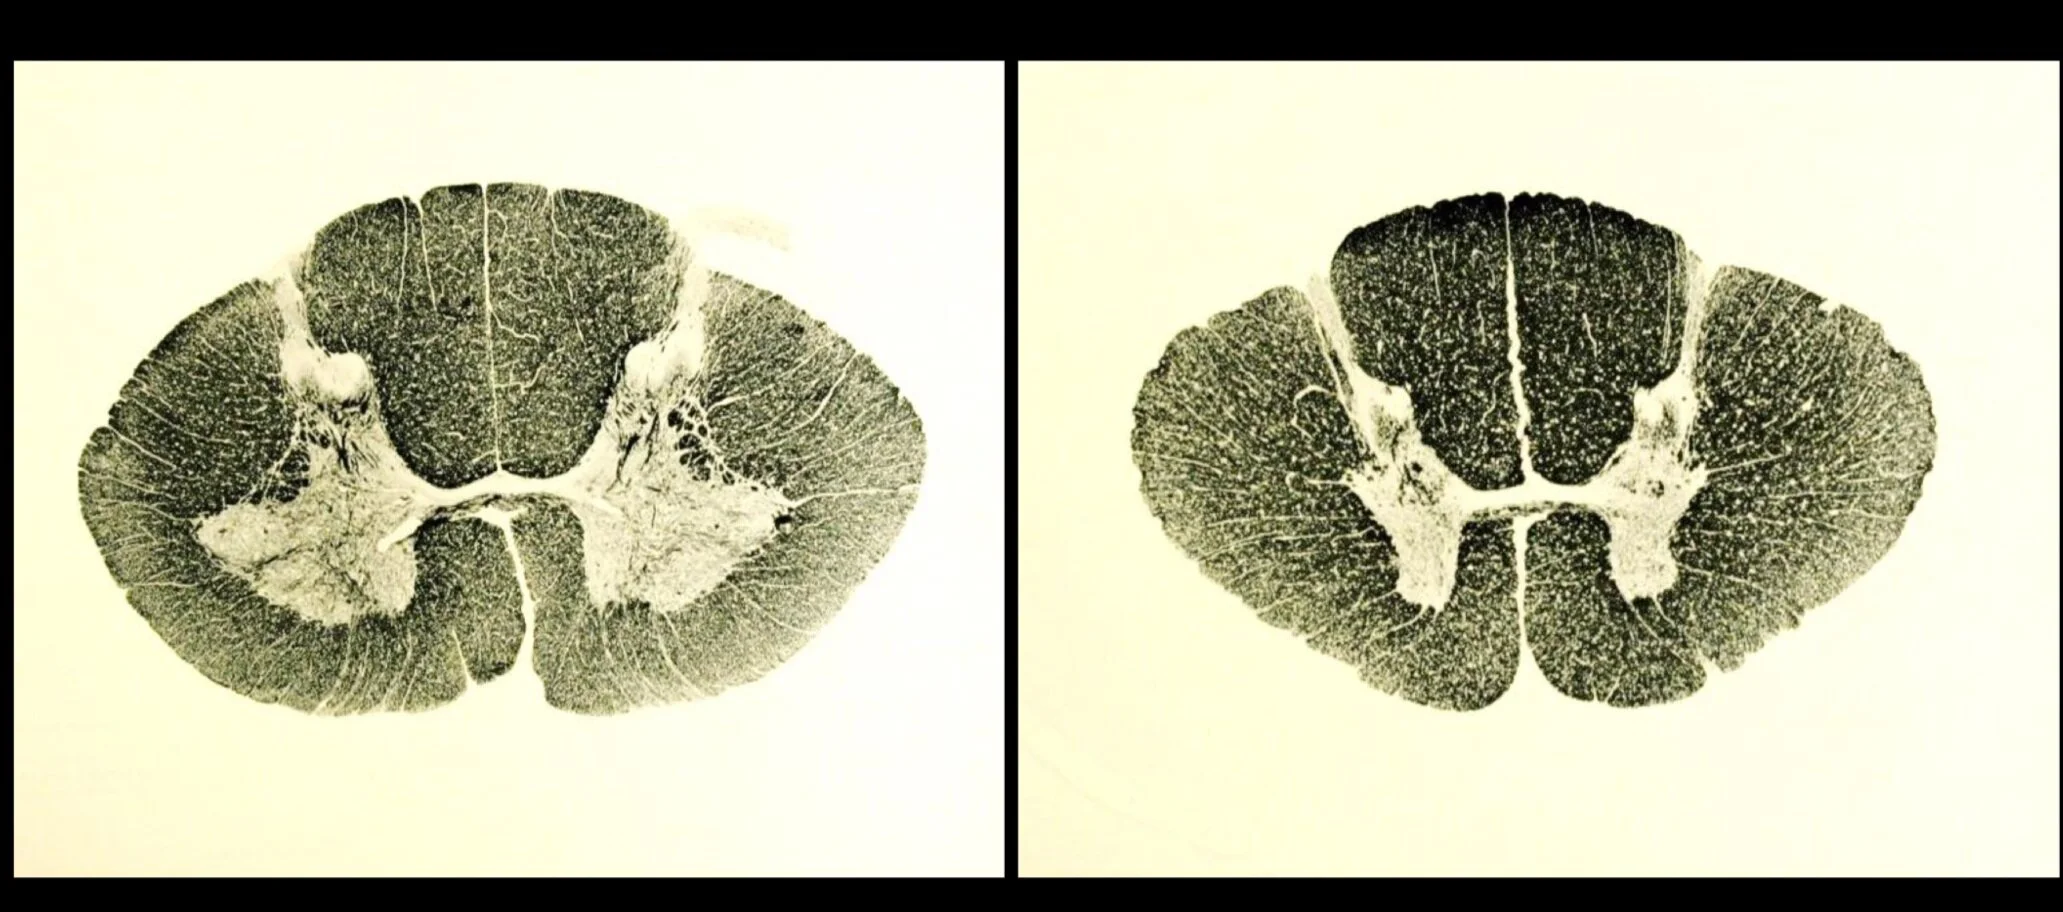

Spinal Cord, Part 1

Spinal Cord, Part 2